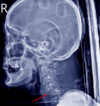

TCE

¿Qué tipo de fractura es esta?

A

Fractura de base de cráneo